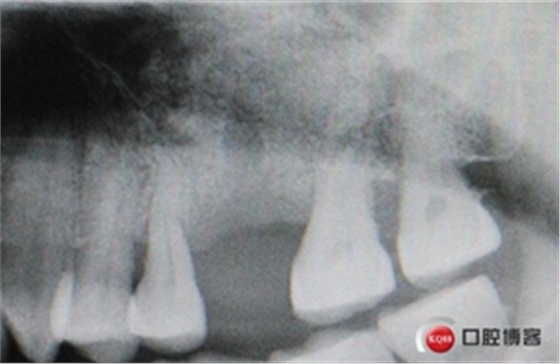

術(shù)后X光片,植骨量充足。

術(shù)后8個月,X光顯示骨量充足,密度明顯增加。

切開翻瓣。

植入一顆4.5x11.5mm長度植體。

植入后X光片。

半年后修復(fù)。